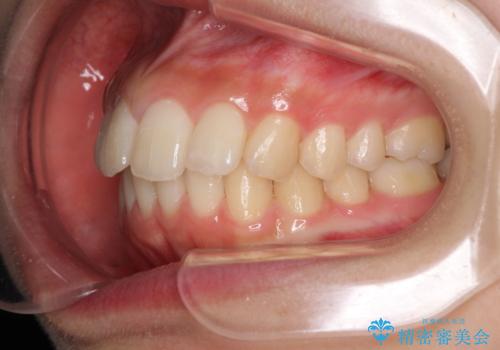

就職前にきれいな歯並びにしたい 大学生のインビザライン矯正

- 就職するまでに歯並びをきれいにしたいとのことで来院された患者様です。

前歯の叢生を気にしていましたが、極力突出感を改善できるようにすることとし、インビザラインにて矯正治療を行うこととしました。

改善の期待できない口元の突出感改善を希望されたため、いたずらに治療期間が延びましたが、きっちりと仕上がりました。